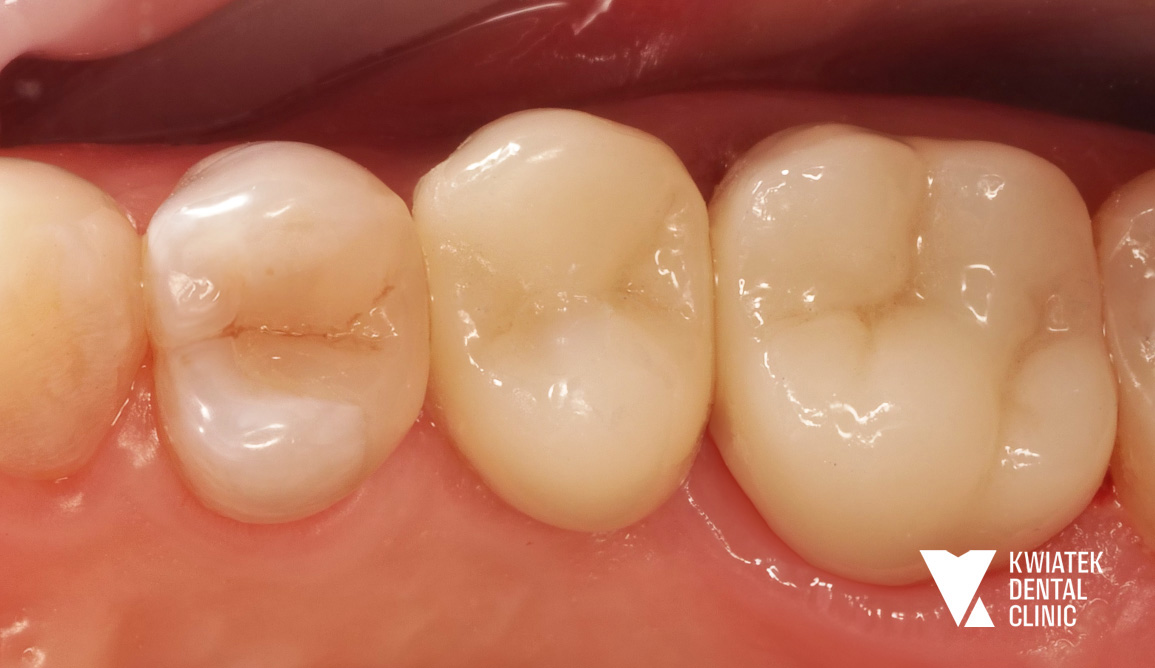

Pełna rekonstrukcja zwarcia i estetyki - historia wymagającej metamorfozy

Pacjent zgłosił się do kliniki z zaawansowanymi problemami stomatologicznymi: licznymi ubytkami próchnicowymi, brakami zębowymi, starciem zębów oraz zaburzeniami zwarcia. Leczenie obejmowało kompleksową diagnostykę, leczenie zachowawcze i endodontyczne, zabiegi chirurgiczne, implantację oraz wieloetapową odbudowę protetyczną. Efektem terapii jest perfekcyjnie zbalansowany zgryz, najwyższy komfort funkcjonowania oraz naturalnie piękny uśmiech, który podkreśla indywidualny charakter pacjenta i pozwala mu w pełni cieszyć się nim każdego dnia.